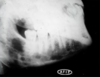

What is this radiographical finding?

Metastatic Carcinoma to Jaw Bones

C. Periapical image of a metastatic lesion of breast carcinoma; note the irregular widening of the periodontal membrane spaces and patchy sclerotic bone reaction, especially around the roots of the molars